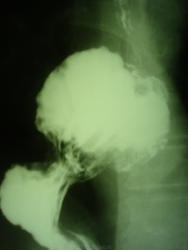

Вот здесь типичная скользящая аксиальная грыжа в форме «бутона» и никаких «грибочков» сбоку, со своей отдельной ножкой-шейкой)). Как там.

Позволю себе вмешаться в мужской спор. Коллеги, все-таки "аксиальная" и "скользящая" - синонимы. Подразделяются они на: а. фиксированные и нефиксированные; б. кардиальные, кардио-фундальные, желудочные. В данном случае имеем аксиальную фиксированную кардио-фундальную грыжу (почти желудочную)...